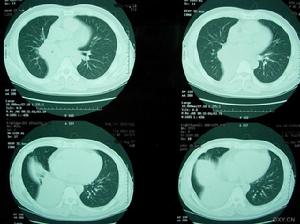

急性侵襲型肺麴黴病血常規:嗜酸性細胞升高。IgG沉澱素90%以上陽性。血清總IgE明顯升高。胸部X線表現為不同形態的肺浸潤,以支氣管肺炎最常見。多發性局灶性浸潤常分布在周圍肺野。部分病例表現類似肺栓塞或梗死。大葉肺實變和粟粒狀病變亦有所見。隨著病變進展,常常出現肺空洞,其中亦可形成急性麴黴球。並發胸腔積液時則見相應X線徵象。